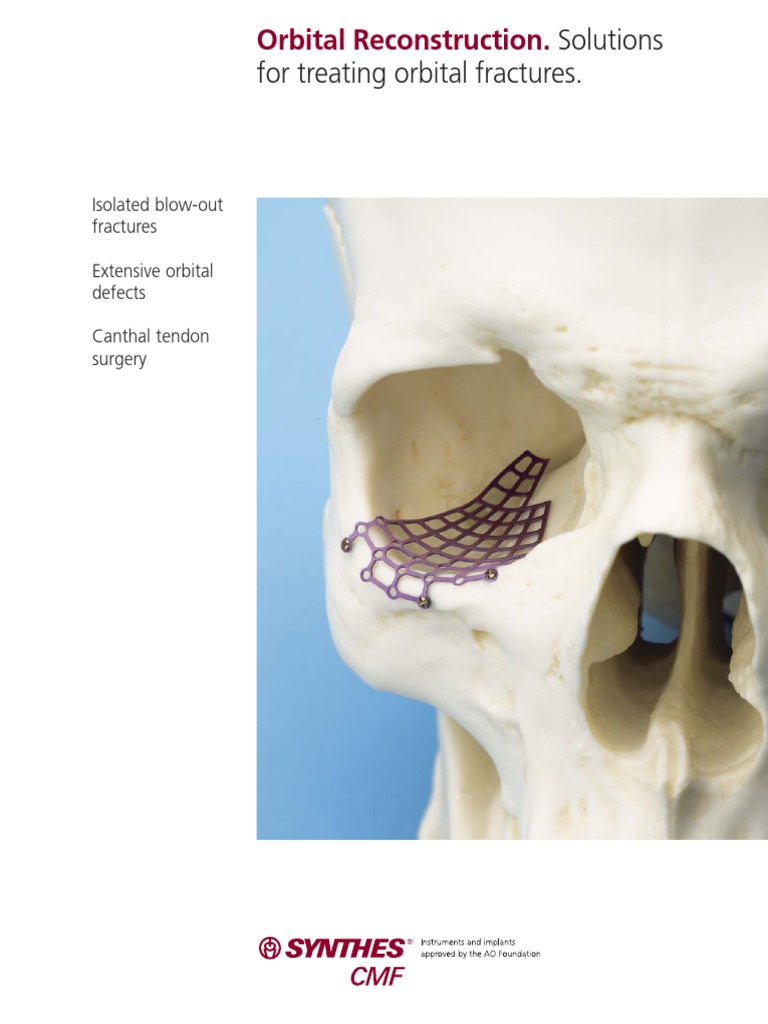

Titanium Orbital Plates. For reconstruction of medial wallsynthes Titanium Plate Orbital Fracture — orbital floor fractures are a painful and disabling result of blunt trauma to the face, commonly causing emergency. In patients where there is significant loss of the medial wall and. — bioresorbables, titanium plate, and porous polyethylene were used. — orbital trauma is a frequent cause of damage to both bony, soft tissue and neurovascular structures. Titanium Plate Orbital Fracture.

Orbital Reconstruction. Solutions For Treating Orbital Fractures PDF Titanium Plate Orbital Fracture — 3d preformed titanium meshes can reconstruct inferomedial fractures with the same accuracy as customized. — orbital trauma is a frequent cause of damage to both bony, soft tissue and neurovascular structures in the. — we use titanium mesh to repair orbital wall defects and titanium plate to repair fractures of orbital margin and. In patients where. Titanium Plate Orbital Fracture.